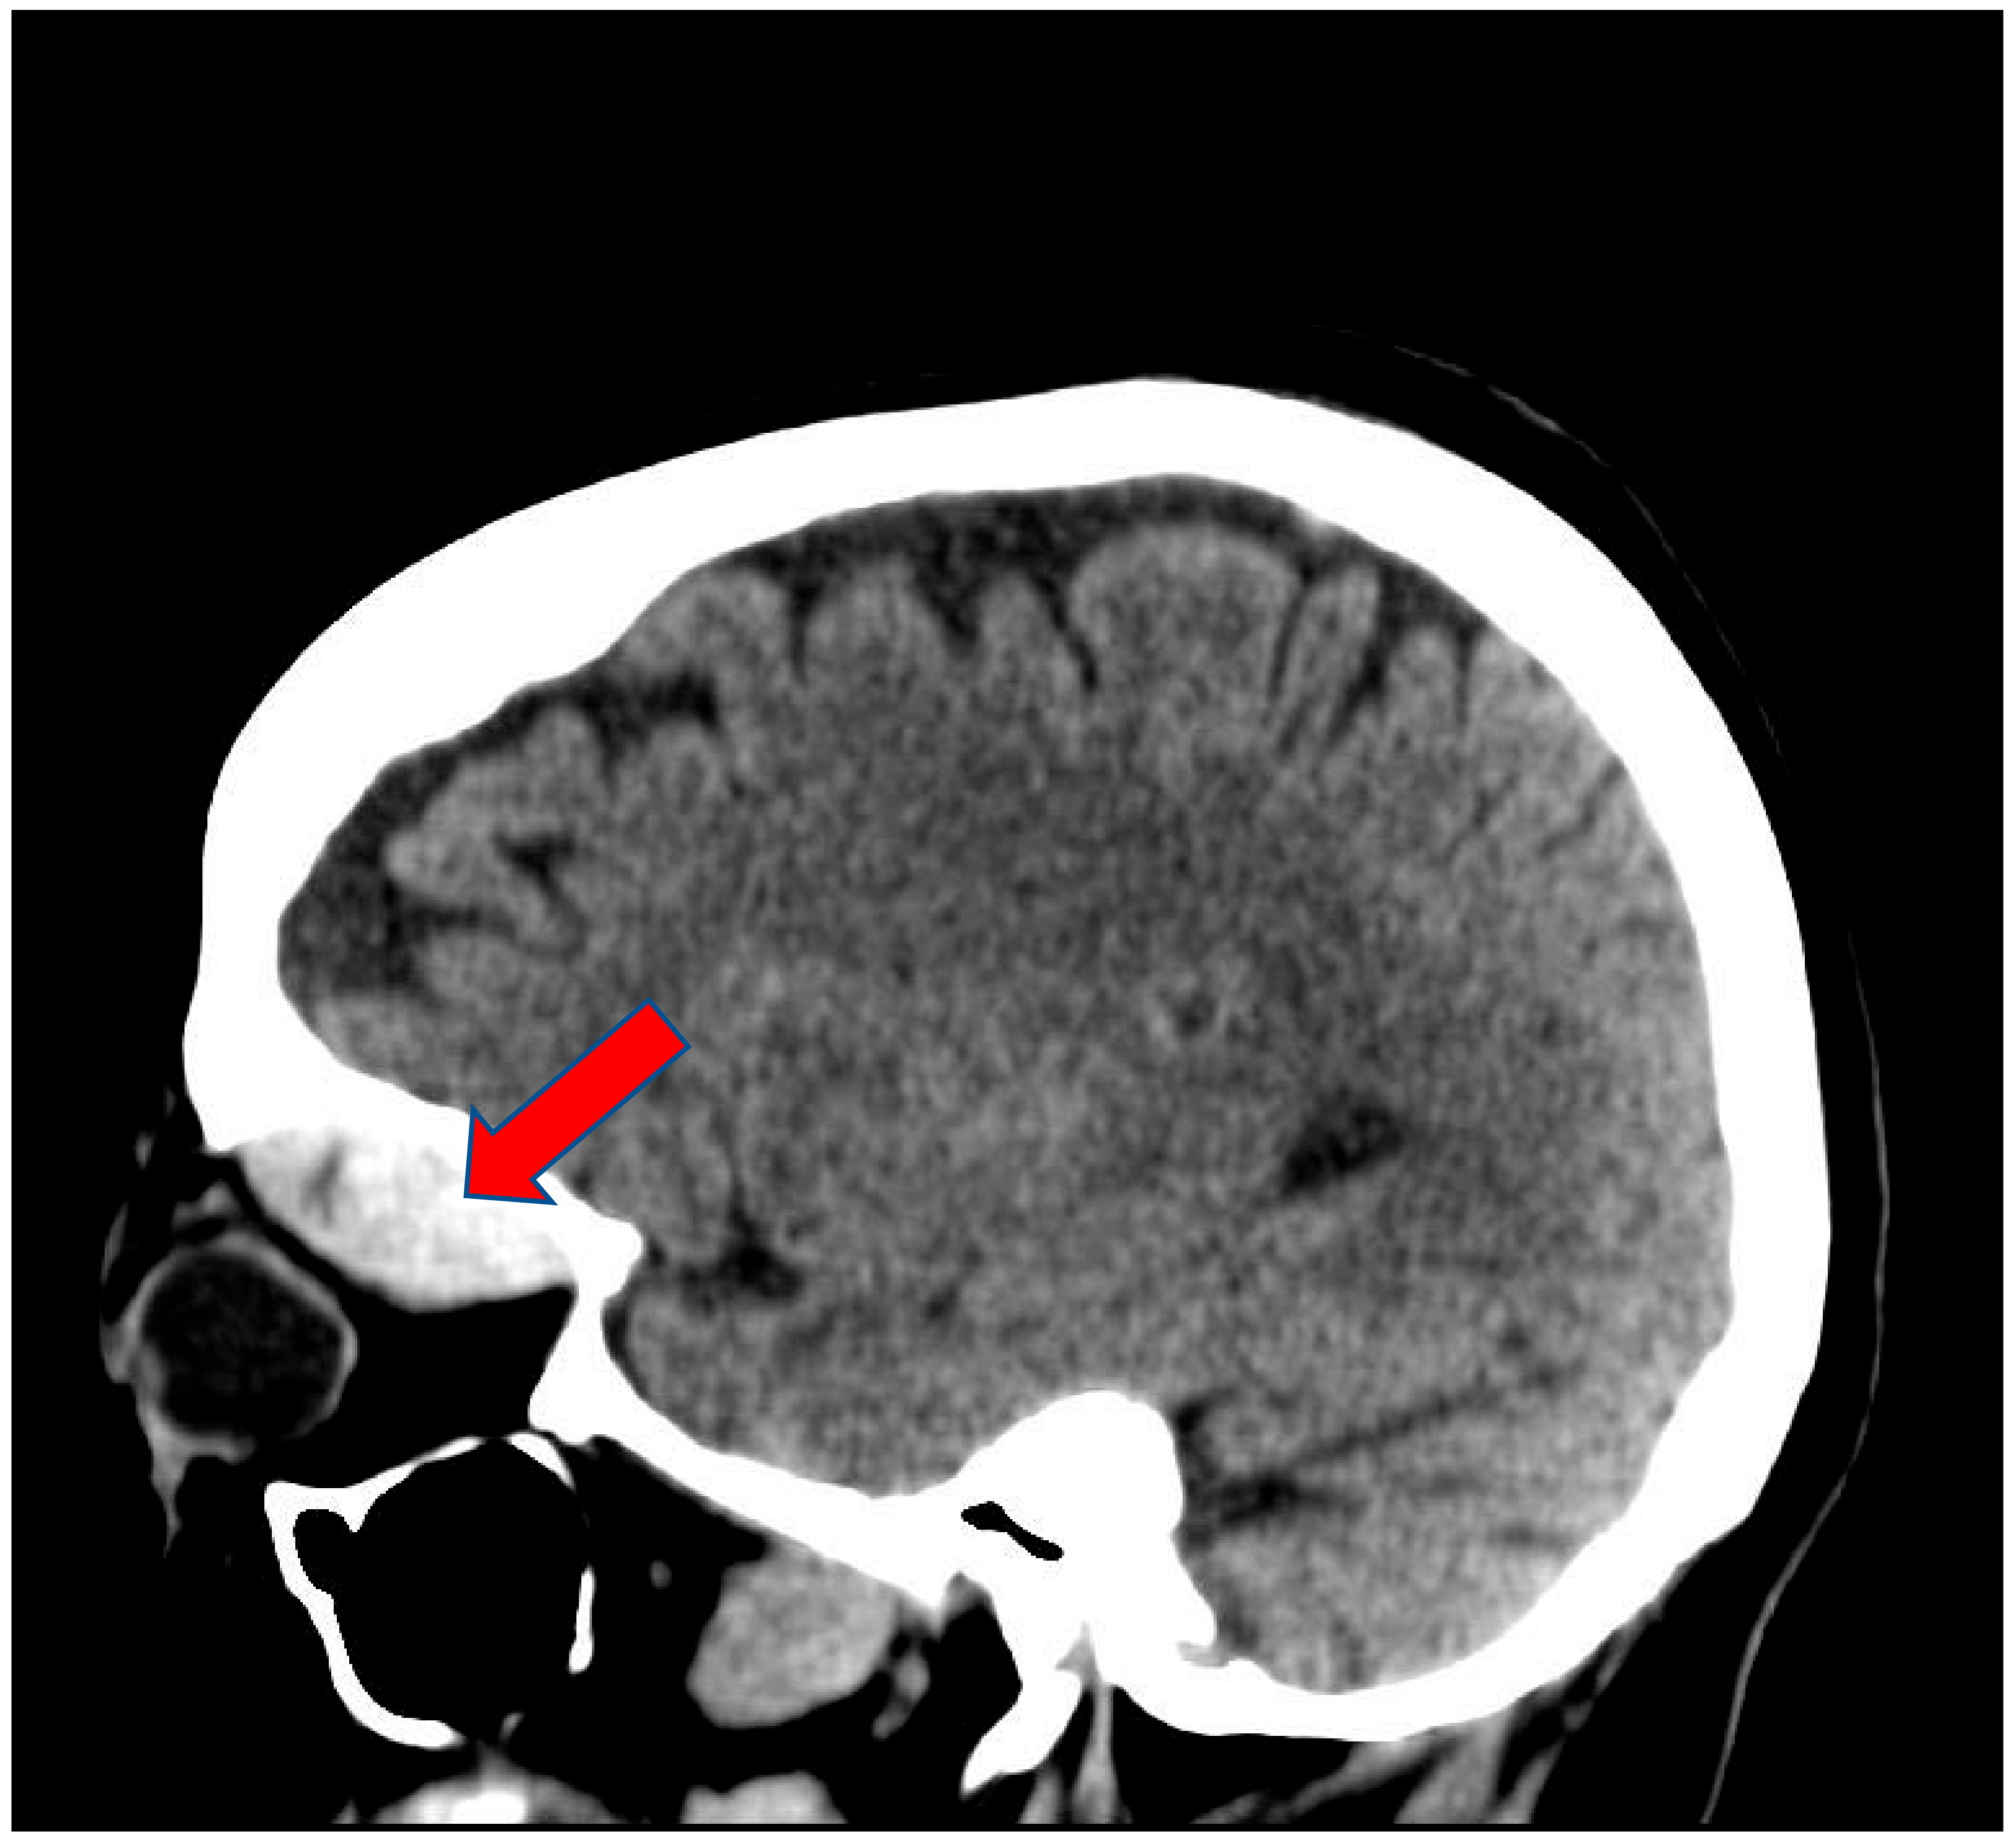

2. Case Presentation